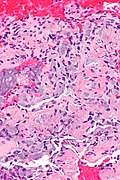

- Spindle cells without atypia and moderate lightly eosinophilic cytoplasm without distinctive cell borders.

- Eosinophilic matrix - described as "gungy" (shabby).[6]

- HPC-like vessels.

- Osteoclast-type giant cells.

- +/-Hemorrhage.

- +/-Calcifications.

- Phosphaturic mesenchymal tumour - alt -- high mag.jpg

PMTMCT - high mag. (WC)